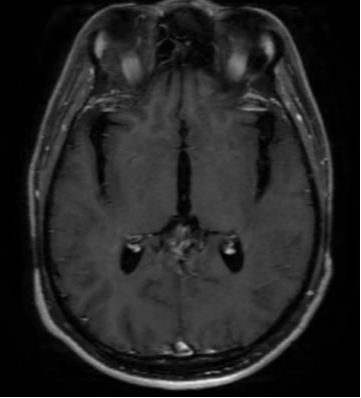

今天门诊来的一对夫妇,带着10岁的患者走进诊室,孩子看上去脸色苍白、口唇发绀、精神状态不佳,经过患者父母描述,孩子近期出现无明显诱因出现发热,至当地卫生所进行采用阿奇霉素结合头孢菌素类抗菌药物进行抗感染治疗,用药后出现精神差、抽搐、表现为意识不清、双眼凝视等现象。主诉:发热、乏力、无痰性干咳、头部持续胀痛、腹泻、呕吐、意识障碍、口唇发绀、意识不清、惊厥、脑膜刺激征、颈部强直、呼吸循环衰竭。鉴于患者的病情,遂立即进行相关检查,脑脊液常规生化:糖定性(+),脑脊液单纯疱疹病毒DNA(+)。头颅磁共振成像(MRI)示:双侧额颞顶部异常信号,MRI冠状位(T1增强)示双侧颞叶、侧脑室旁、岛叶及扣带回、右侧眶额回脑实质略肿胀,其内见片状长T1、长T2信号,DWI见高信号,ADC减低不明显,增强检查右侧颞叶不均匀异常强化。考虑颅内感染。经过医生诊断结合既往病史、家族遗传史、主诉及一系列的检查结果显示,患者被确诊为单纯疱疹病毒性脑膜炎。

图一 头颅磁共振成像(MRI)